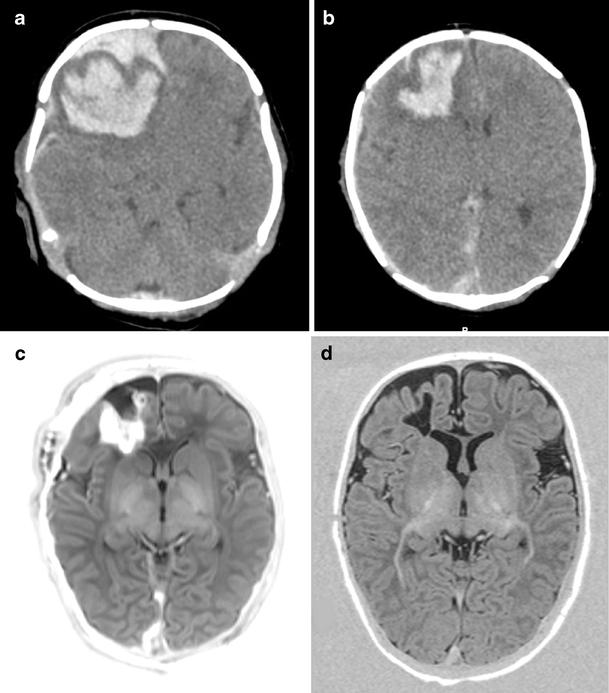

Seventeen of the 53 term infants had infratentorial ICH, 20 had supratentorial ICH, and 16 had a combination of the two. Seizures were the most common presenting symptom (71.7%), another ten infants (18.9%) presented with apneic seizures, and five infants had no clinical signs but were admitted to our NICU because of perinatal asphyxia (n=2), respiratory distress (n=2), and development of posthemorrhagic ventricular dilatation (n=1). Continuous amplitude-integrated electroencephalography recordings were performed in all infants. Clinical or subclinical seizures were seen in 48/53 (90.6%) infants; all received anti-epileptic drugs. Thirteen of all 53 (24.5%) infants died. The lowest mortality rate was seen in infants with supratentorial ICH (10%). Three infants with a midline shift required craniotomy, six infants needed a subcutaneous reservoir due to outflow obstruction, and three subsequently required a ventriculoperitoneal shunt. The group with poor outcome (death or developmental quotient (DQ) <85) had a significantly lower 5-min Apgar score (p=.006). Follow-up data were available for 37/40 survivors aged at least 15 months. Patients were assessed with the Griffiths Mental Developmental Scales, and the mean DQ of all survivors was 97 (SD=12). Six infants (17%) had a DQ below 85 [two of them had cerebral palsy (CP)]. Three infants developed CP (8.6%); one had cerebellar ataxia, and two had hemiplegia.

ICH with parenchymal involvement carries a risk of adverse neurological sequelae with a mortality of 24.5% and development of CP in 8.6%. The high mortality rate could partly be explained by associated perinatal asphyxia. Infants with supratentorial ICH had a lower, although not significant, mortality rate compared with infants with infratentorial ICH and infants with a combination of supratentorial ICH and infratentorial ICH. In spite of often large intraparenchymal lesions, 30 of the 34 survivors without CP (88.2%) had normal neurodevelopmental outcome at 15 months.